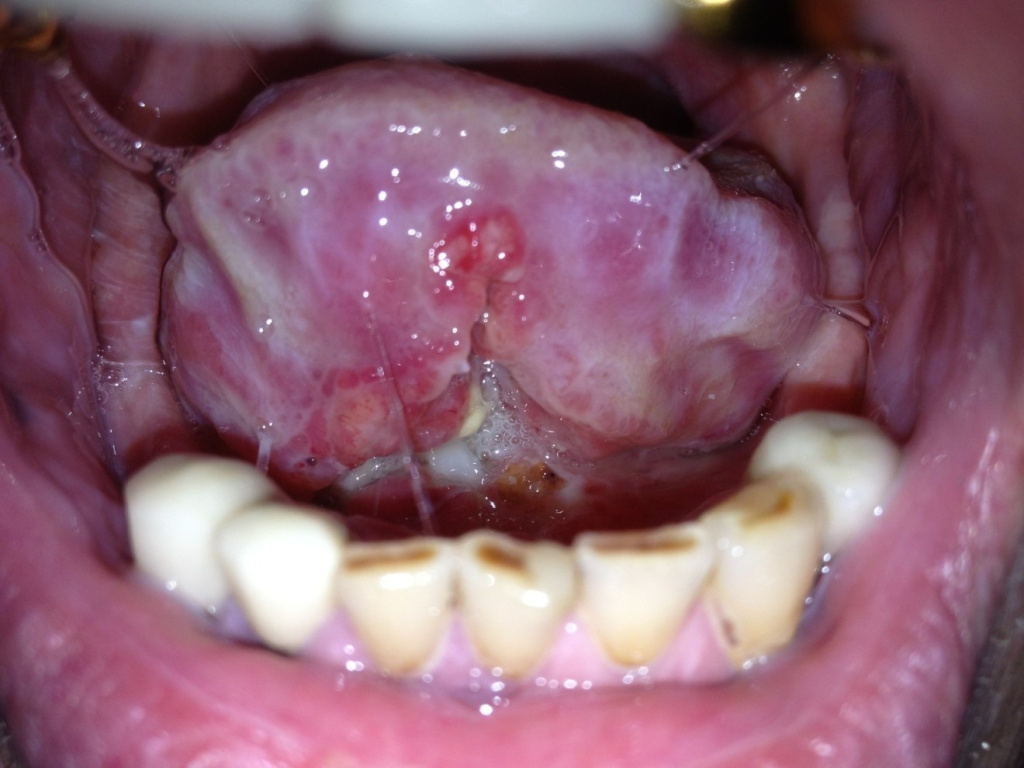

Фото первичной опухоли, плоскоклеточный рак слизистой дна полости рта с переходом на язык

Удаление опухоли ротовой полости с одномоментной реконструктивной пластикой дефекта